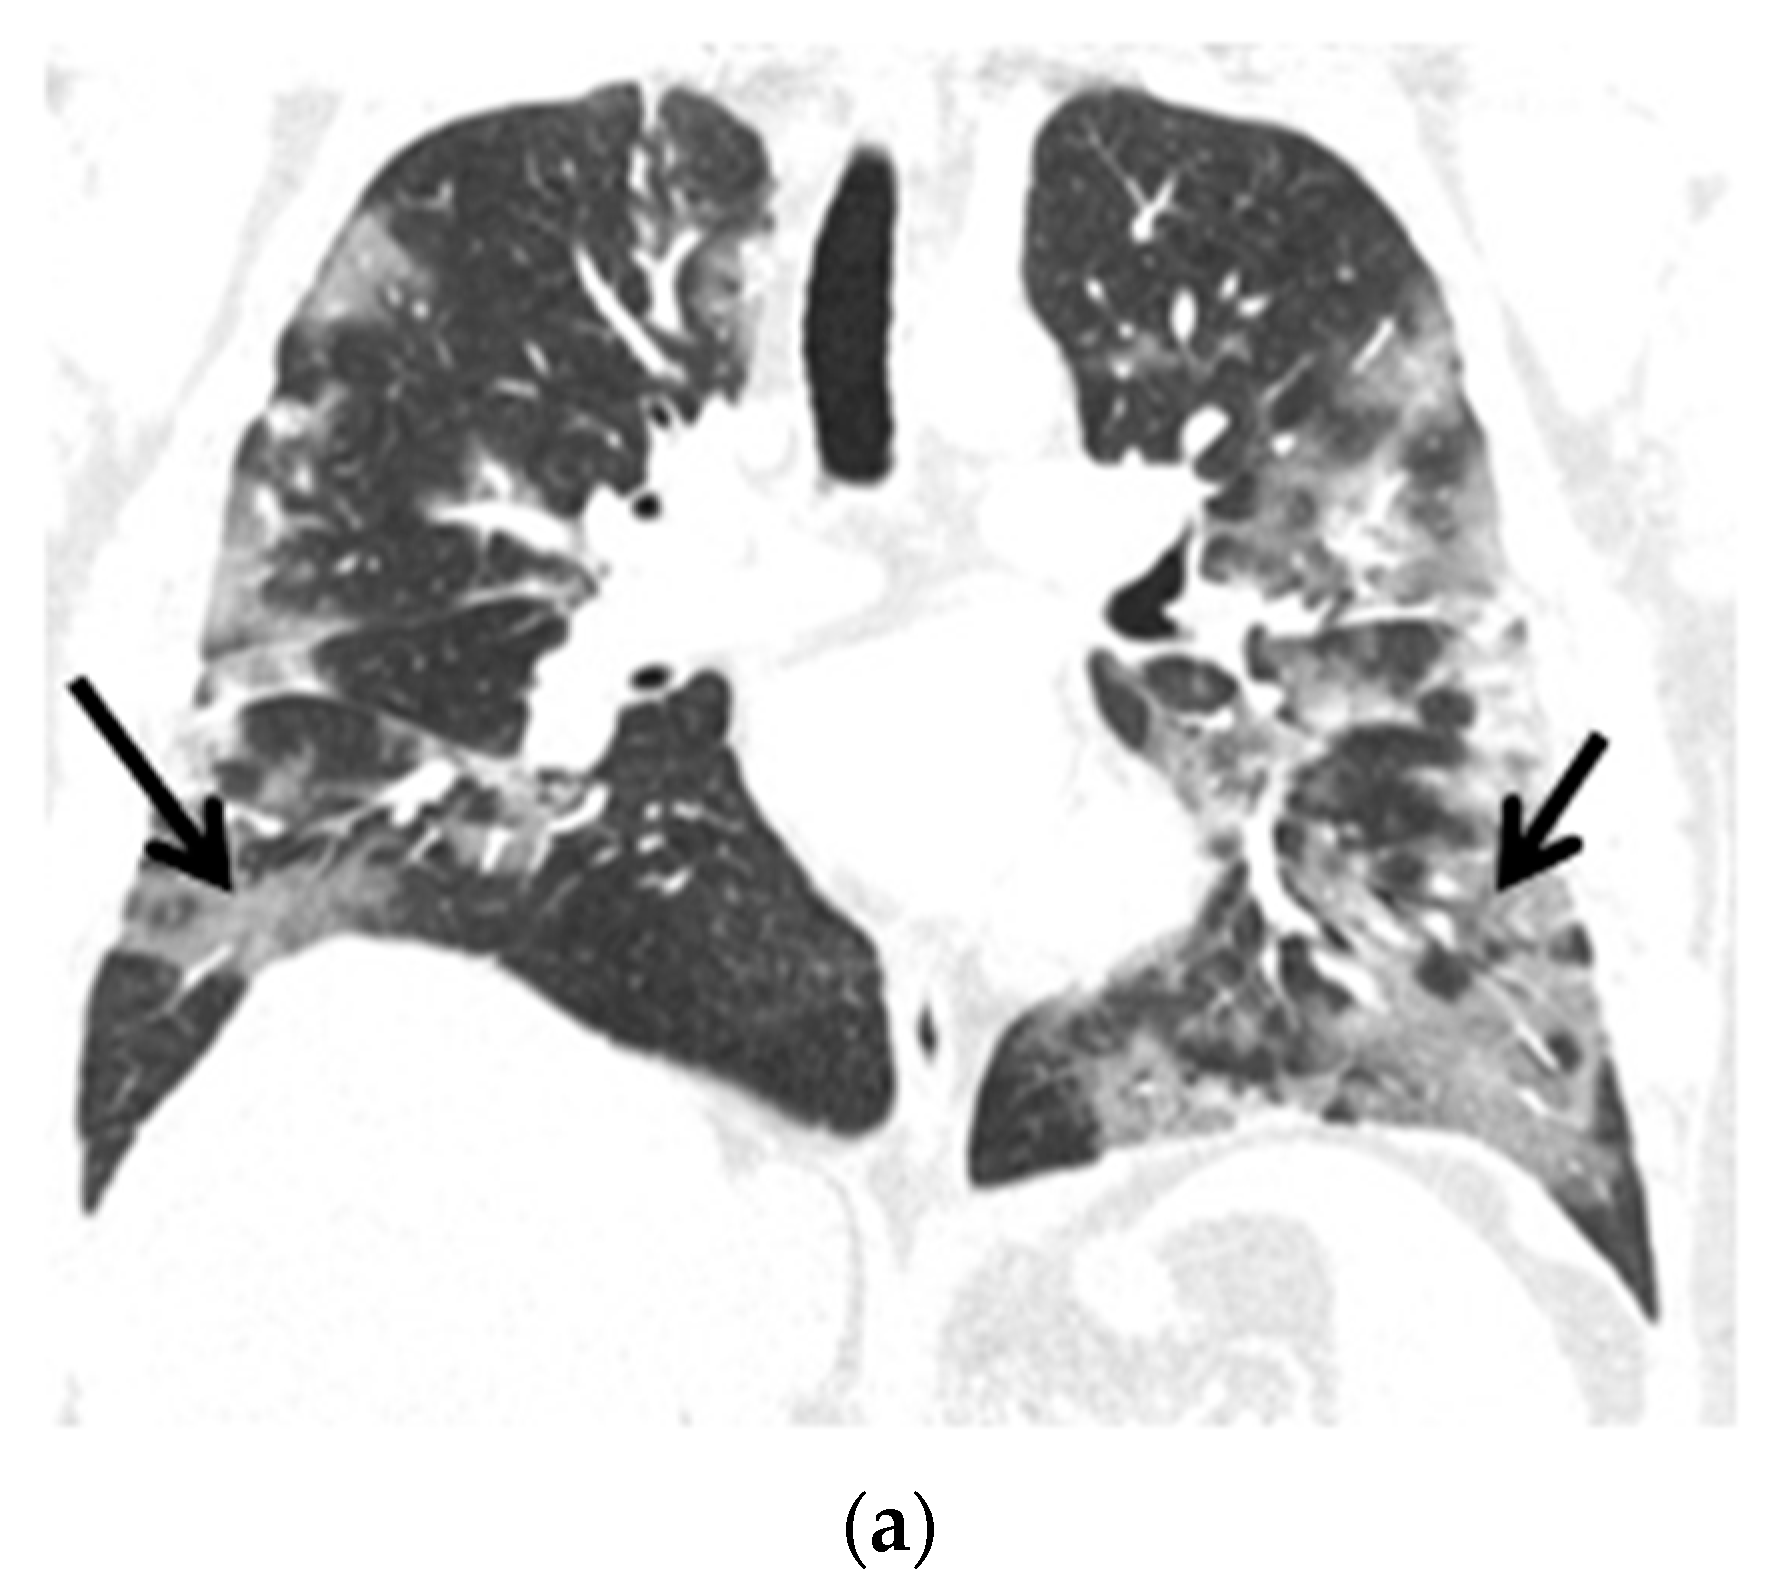

Figure 3.

(a) Chest CT scans (lung window, coronal view) show patchy ground-glass opacities in accordance with COVID-19 dominant in the peripheral zones of the lower lungs (black arrows); (b) Chest CT scans (lung window, coronal view) after six months of follow-up show resolution of lung lesions (black arrows).